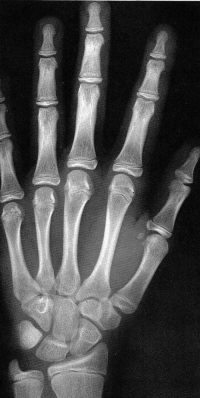

Sexo Feminino

3 meses